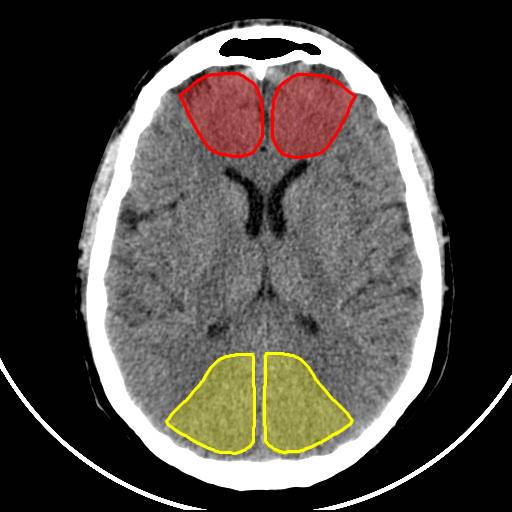

Analyse quantitative

Territoire de l’artère cérébrale postérieure